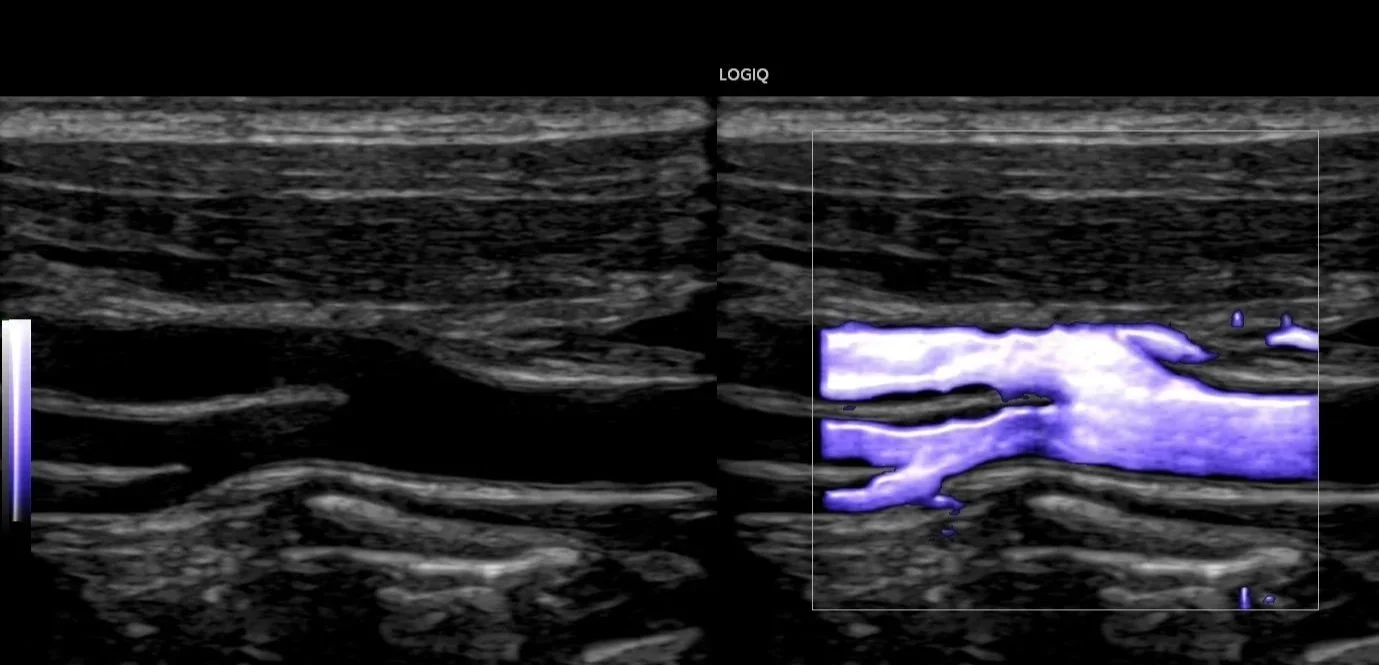

Doppler and vascular ultrasound focus on blood flow and blood vessels. This technique can detect blockages, narrowing, or abnormalities in arteries and veins, helping diagnose circulatory issues and guide treatment.

Doppler/Vascular

Arterial Lower/Upper Limb

Deep Vein Thrombosis (DVT) Upper/Lower Limb

Chronic Venous Insufficiency (CVI)

Carotids

Renal Doppler

Aorta Doppler